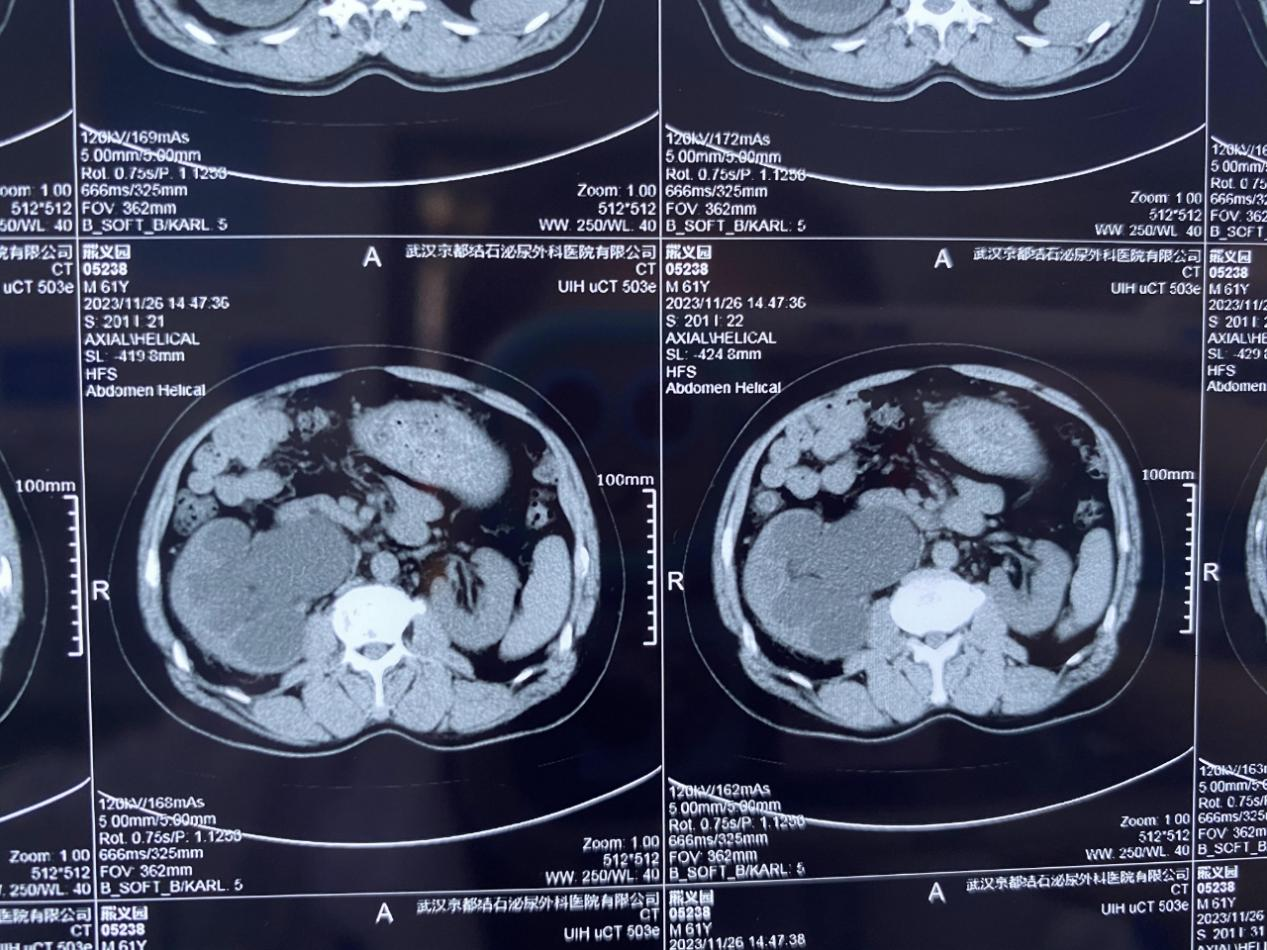

經(jīng)查,熊師傅的右輸尿管上段有多發(fā)結(jié)石梗阻,其中最大一顆結(jié)石有2.5cm,右腎已出現(xiàn)重度積水、腎功能不全等問題。該院泌尿外科主治醫(yī)師潘良超指出:“如果繼續(xù)拖延下去,右腎積水將會越來越嚴(yán)重,感染加劇,還會持續(xù)損害腎臟功能,屆時右腎可能將徹底“報廢”了,必須馬上手術(shù)處理?!?/span>

為了保住患者岌岌可危的右腎,在完善相關(guān)術(shù)前檢查后,該院泌尿結(jié)石團(tuán)隊為其制定并實施了電子軟鏡無創(chuàng)保腎取石術(shù)。手術(shù)全程1個多小時,成功將其梗阻在輸尿管的結(jié)石清除取出,積水問題也得到了有效緩解,右腎危機(jī)得以正式解除。